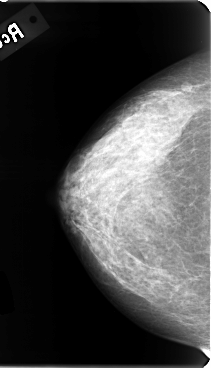

B_3085_1.RIGHT_CC

RIGHT_CC LINES 4776 PIXELS_PER_LINE 2736 BITS_PER_PIXEL 12 RESOLUTION 50 NON_OVERLAY